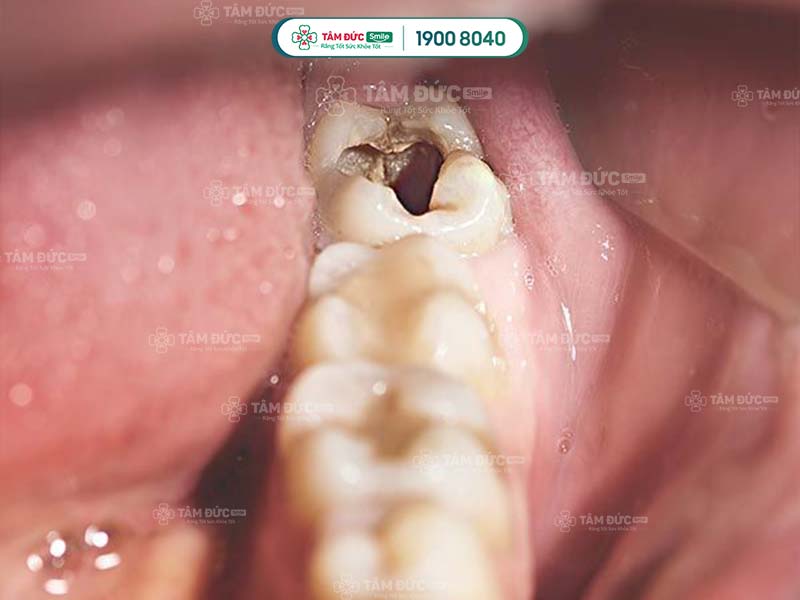

1.1. Bề mặt răng có các đốm nâu đen

Đây là dấu hiệu điển hình nhất khi răng khôn bị sâu. Các đốm nâu đen này xuất hiện do vi khuẩn sâu răng tấn công và ăn mòn men răng, gây sâu răng.